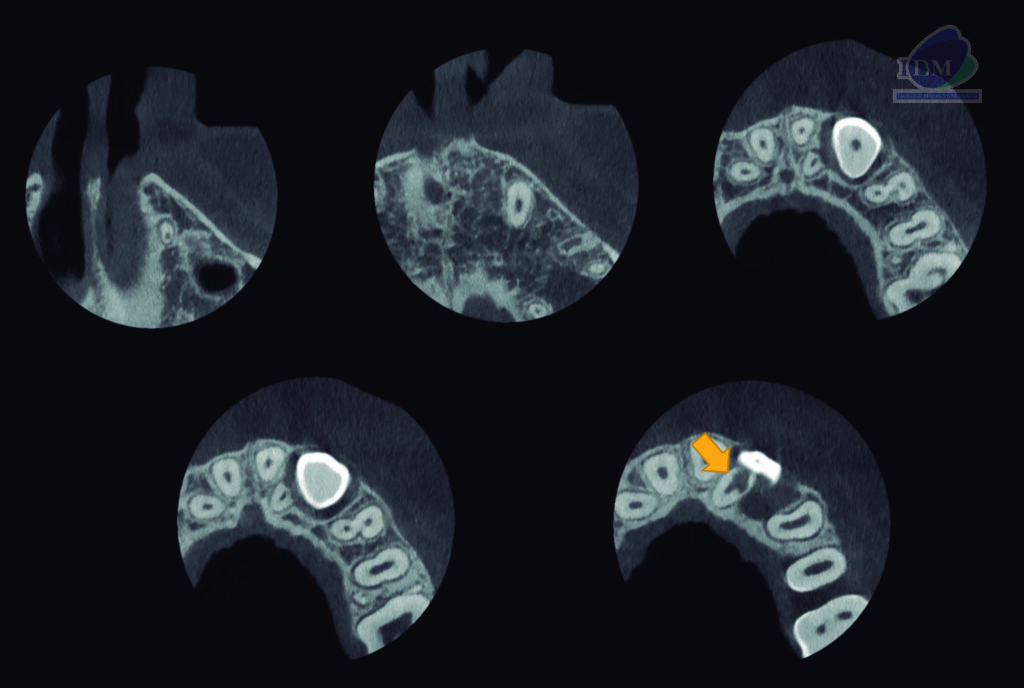

A la evaluación de la tomografía computarizada de campo reducido se observa la porción coronaria de la pieza 23 orientada hacia vestibular y ocasionando el desplazamiento palatino de la pieza 22 así como la reabsorción radicular externa vestibulodistal del tercio medio que también compromete conducto pulpar. Finalmente se observa el tercio apical de la pieza 23 en formación y en contacto con el piso de fosa nasal y seno maxilar.

CORTES AXIALES